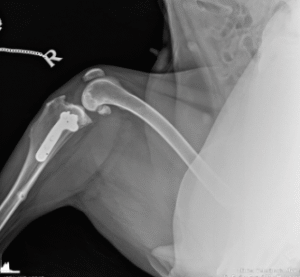

Gli interventi ortopedici sono procedure chirurgiche che trattano patologie dell’apparato muscolo-scheletrico, come fratture, lussazioni, displasie e problemi articolari. Si occupano di correggere deformità, riparare lesioni e migliorare la mobilità degli animali.

Displasia dell’anca: Trattamento chirurgico per correggere questa patologia.